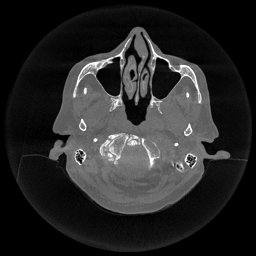

III-D Real Clinical Data Experiment

The experimental results on clinical head data are shown in Fig. 4. The reference images were reconstructed using the fast iterative shrinkage-thresholding algorithm (FISTA) with total variation regularization from non-truncated projection data. In the WCE reconstructions (Fig. 4(b)), severe truncation prevents accurate recovery of anatomical structures outside the FOV. Despite being trained solely on simulated data with a domain gap, all deep learning models can restore a substantial portion of the missing anatomy. Among them, the diffusion-based methods recover soft-tissue boundaries more faithfully than the conventional deep learning approach FBPConvNet, highlighting their stronger image generation capability. However, cDDPM reconstructions exhibit more noticeable noise than those from other methods, consistent with the simulated data results. The patchDiffusion model introduces artifacts within the FOV, likely due to its patch-wise processing strategy. While I2SB shares the same limitations as other diffusion models in perfectly restoring soft-tissue detail, it produces fewer residual noise patterns and fewer artifacts within the FOV boundaries. Overall, Fig. 4 demonstrates the strong efficacy of I2SB in reconstructing real CBCT data.